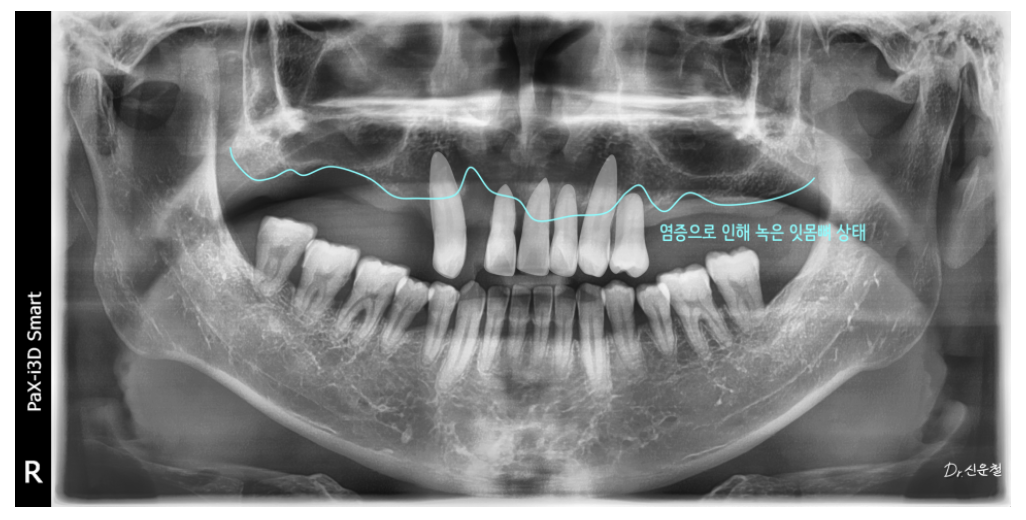

앞니는 일부 남아 있었지만

오랜 염증으로 인해 치아를 지지하던 뼈가 많이 흡수된 상태였습니다.

잇몸뼈가 줄어들면

잇몸은 함께 내려가고

내려간 잇몸은 다시 올라오지 않습니다

이 경우 보철물을 만들면

앞니가 길어 보일 수밖에 없는 구조가 됩니다.

위턱·아래턱 상태 정밀 진단

위턱

남아 있는 치아 중 좌측 견치 1개만 보존 가능

견치는 뿌리가 길어 치조골 지지력이 비교적 좋은 치아

그 외 치아는 염증이 심하고 치조골 지지가 어려운 상태